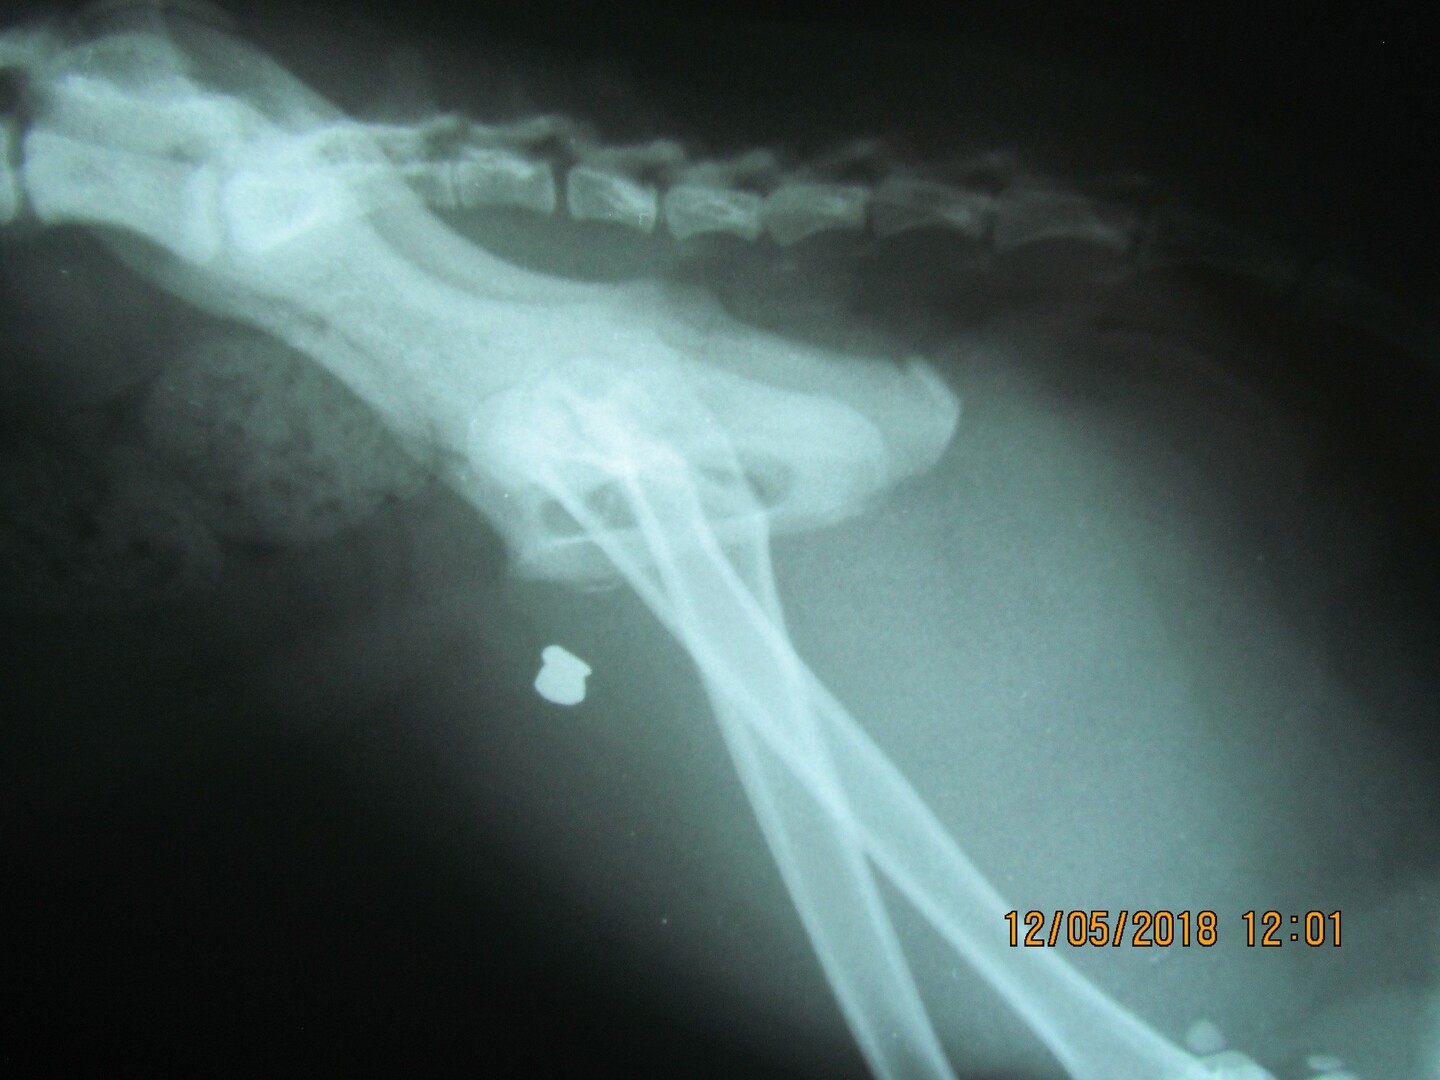

Bereits am Montag, 07.05.2018, entdeckte die Eigentümerin im Beckenbereich des linken Hinterbeines ihres zutraulichen, grau-weißen Katers „Hugo“ (1,5 Jahre) eine kleinere, aber blutende Verletzung. Nachdem die Wunde trotz tierärztlicher Versorgung nicht verheilen wollte, wurde der Kater am 12.05.2018 geröntgt. Hierbei kam zu Tage, dass sich ca. 5 bis 6 Zentimeter (!) im Muskelgewebe ein 4,5 mm durchmessendes Luftdruckgeschoss befand. Aufgrund der außergewöhnlichen Tiefe des Geschosses ist davon auszugehen, dass vermutlich aus nächster Nähe auf das arme Tier geschossen wurde.